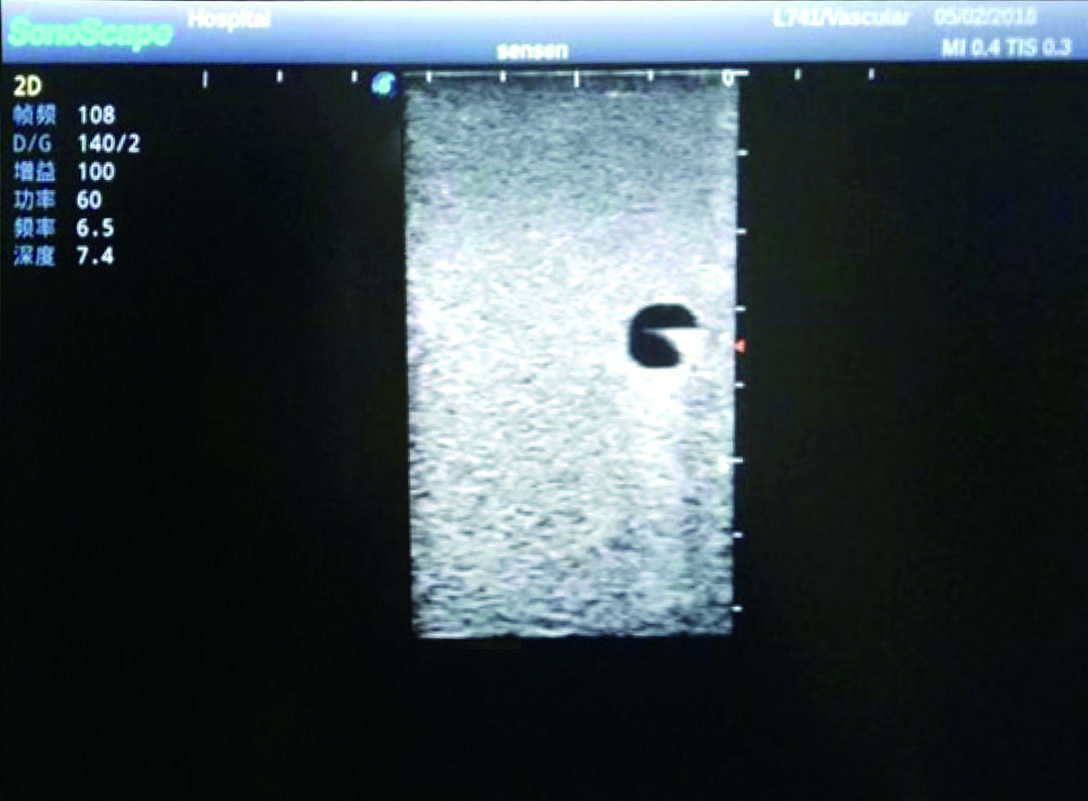

Model TYE1510.1

It is a model covering up from lobulus auriculae plane to the umbilical plane, and it has anatomical structures like clavicle, rib, sternocleidomastoid, jugular vein and basilic vein.

1)   Made of high molecular polymer ultrasound material, close to the real skin

2)   It can be used by real ultrasound machines

3)   Clear and real images of the tissues and organs (basilic vein and superior vena cava)